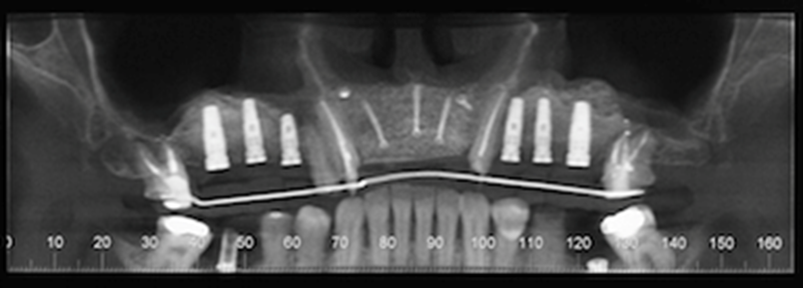

At the 8-months follow-up, a CBCT scan showed consolidation of the grafted material with the recipient bone (Figure 6). A second surgical procedure was conducted under local anesthesia and oral sedation in order to remove the titanium mesh. At this appointment, the pre-maxilla showed to be significantly augmented (Figure 7) with the dimension of 14 mm in height and 10 mm in width. The bone characteristics were soft, erythematous, with a cancellous texture. Four dental implants (Biomet 3I certain®, USA) were inserted, with no more than 25 Ncm2 of primary stability (Figure 8). The implants were uncovered 6 months later for initiation of the prosthetic rehabilitation using 4 single-unit crowns. One-year follow-up showed to be uneventful (Figure 9).

Figure 6.CBCT scan 8 months post ridge augmentation. Note significant increase in bone augmentation of the pre-maxilla. Presence of implants for sites #2, 3, 4, 11, 12 and 13 after right and left sinus lifts were performed.